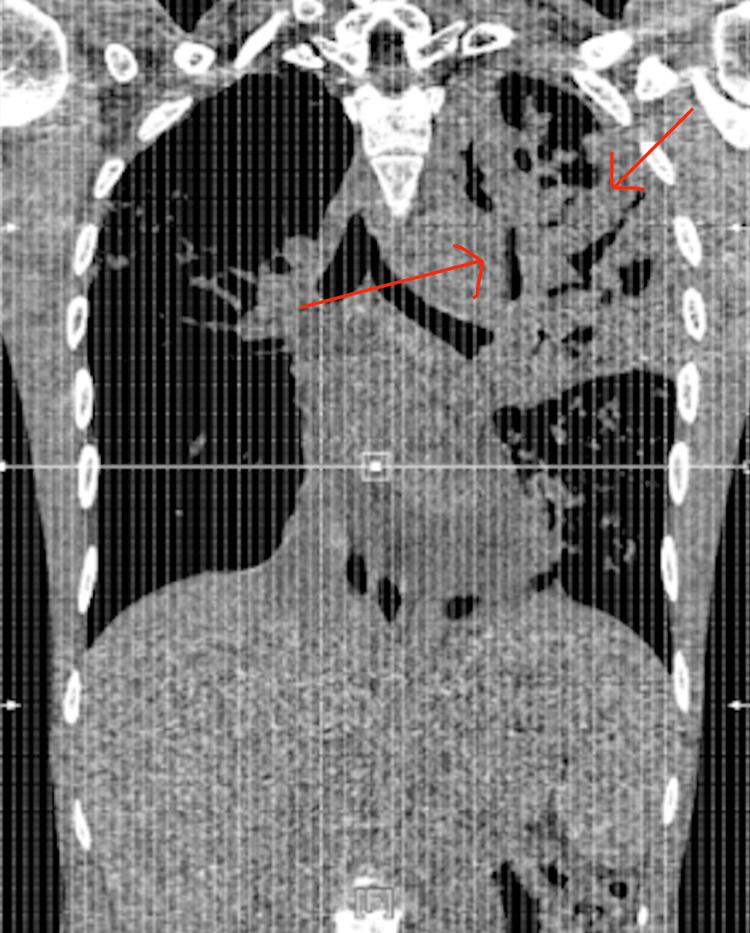

This case presents a 25-year-old Indian male with no significant past medical history presenting to the emergency department (ED) due to two weeks of productive cough with pleuritic chest pain. The patient presented one week earlier to the ED; however, he left against medical advice and was given a 5-day course of Azithromycin 250 mg that minimally improved his symptoms. He returned to the ED shortly after completing the antibiotics and was admitted for further evaluation. He was diagnosed with multifocal pneumonia and started on intravenous antibiotics, then discharged two days later on oral outpatient therapy. One month later, the patient returned to the ED with similar symptoms of worsening productive cough and pleuritic chest pain. CT chest findings revealed a left-sided pleural effusion and large pericardial effusion, which later prompted microbiological testing that confirmed a Mycobacterium tuberculosis infection. A pericardial window was indicated due to tamponade physiology. Although the patient did not present with classic constitutional symptoms of tuberculosis, this case shows the importance of keeping TB high in the differential list among those with recurrent pneumonia and unexplained pleural and pericardial effusions, especially in patients with recent immigration or insidious risk factors, despite how rare pathologies such as pericardial TB can be. Early correct diagnosis and appropriate diagnostic workup, including imaging and microbiological studies, should be ordered to prevent delay in treatment and reduce morbidity.

该病例为一名25岁的印度男性,既往无重大病史,因两周来伴有胸膜炎性胸痛的咳痰性咳嗽而就诊于急诊科(ED)。该患者一周前曾前往急诊科;然而,他自行离院,未遵循医嘱,并接受了为期5天的250毫克阿奇霉素治疗,症状稍有改善。在完成抗生素治疗后不久,他再次返回急诊科并被收治以作进一步评估。他被诊断为多灶性肺炎,并开始接受静脉抗生素治疗,两天后出院并接受口服门诊治疗。一个月后,该患者因咳痰性咳嗽加重和胸膜炎性胸痛等类似症状再次返回急诊科。胸部CT检查发现左侧胸腔积液和大量心包积液,随后进行的微生物检测证实为结核分枝杆菌感染。由于存在心包填塞的生理状况,因此需要进行心包开窗引流术。尽管该患者未表现出典型的结核病全身症状,但该病例表明,对于反复发生肺炎以及出现不明原因胸腔和心包积液的患者,尤其是近期有移民史或存在潜在危险因素的患者,即使心包结核等病理情况较为罕见,在鉴别诊断中也应高度怀疑结核病。应尽早进行正确诊断并开展包括影像学和微生物学研究在内的适当诊断检查,以防止治疗延误并降低发病率。